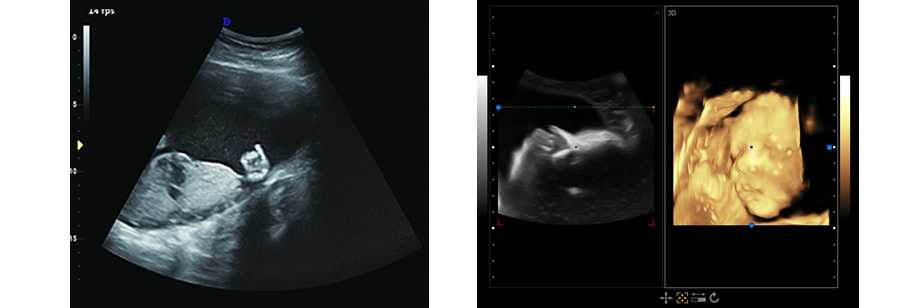

立體光源成像 胎兒容貌實時顯示